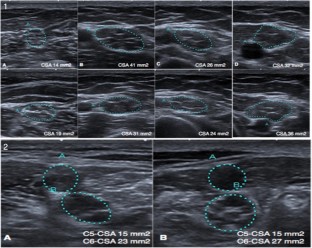

Fig. 1

Fig. 2